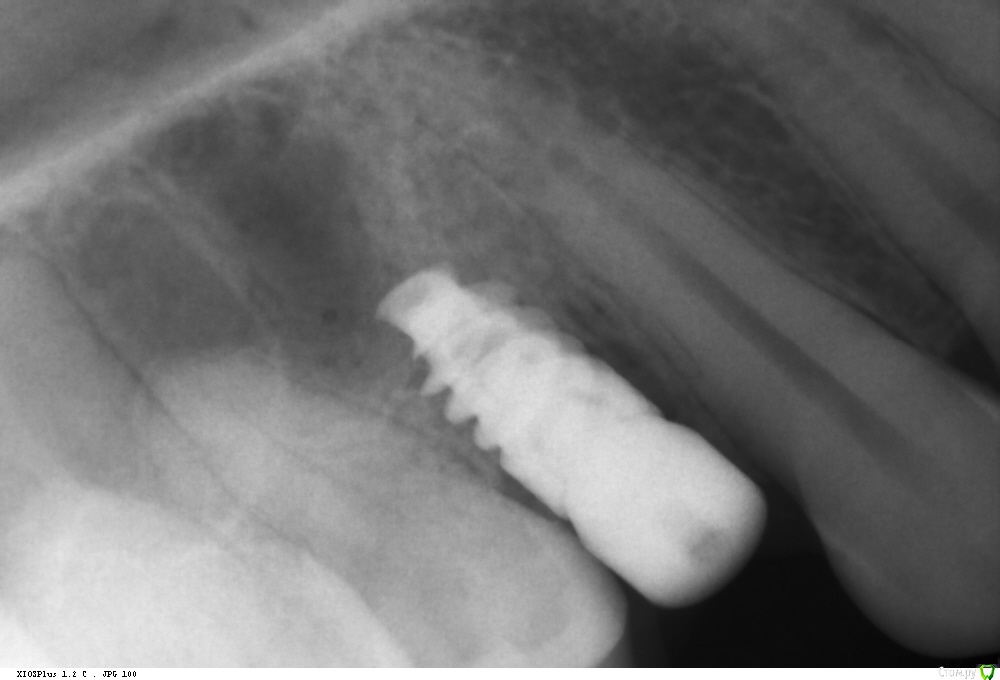

Ponchik Опубликовано 1 августа, 2017 Автор Поделиться Опубликовано 1 августа, 2017 Так и не состоялся тот случай, но сразу же пришла другая пациентка с подобной проблемой. (Проблема в докторе не делающем синус-лифтинга)Планирование Что получилось сразу Формирователь через 3 месяца Ставил AB SPI 4.2 - 8 Фрезой до 6мм, далее вогнутым остеотомом. Изменений в звуке не заметил. Достучал до ограничителя и все.Что в пазухе проблемы увидел, только потом на КТ после имплантации.Всё.Кидайте тапками.P.S.Это был первый имплант на верхней челюсти. Ссылка на комментарий

kamranchick Опубликовано 1 августа, 2017 Поделиться Опубликовано 1 августа, 2017 Так и не состоялся тот случай, но сразу же пришла другая пациентка с подобной проблемой. (Проблема в докторе не делающем синус-лифтинга)Планированиедо.jpg Что получилось сразупосле.jpg Формирователь через 3 месяца 3ме.jpg3мес.jpg Ставил AB SPI 4.2 - 8 Фрезой до 6мм, далее вогнутым остеотомом. Изменений в звуке не заметил. Достучал до ограничителя и все.Что в пазухе проблемы увидел, только потом на КТ после имплантации.Всё.Кидайте тапками.P.S.Это был первый имплант на верхней челюсти.если жалоб нет то все ок Ссылка на комментарий